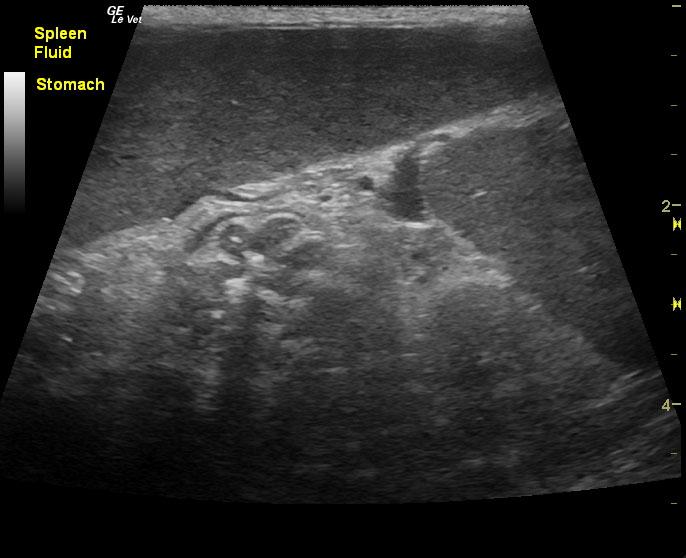

A 15-year-old neutered male DSH cat was presented for evaluation of polyphagia, weight loss, and severe splenomegaly. Abnormalities on CBC and serum biochemistry included leukocytosis, mild hypoalbuminemia, and an elevated BUN 42.